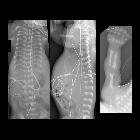

Newborn with

respiratory distress. CXR AP (left) and lateral (center) show extremely short ribs resulting in a very small thorax and thus low lung volumes. AP radiograph of the upper extremity (right) shows a short humerus and an extra digit attached to the fifth digit.The diagnosis was short rib polydactaly syndrome with post axial polydactaly.